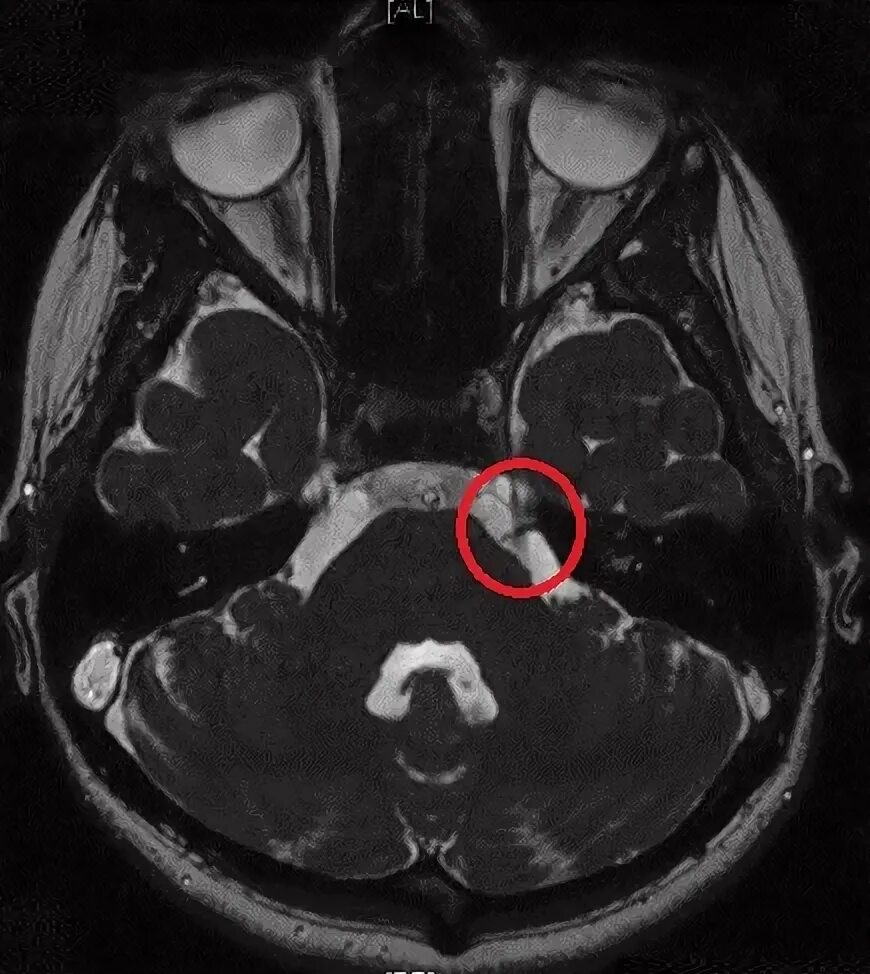

Нейроваскулярный конфликт нерва